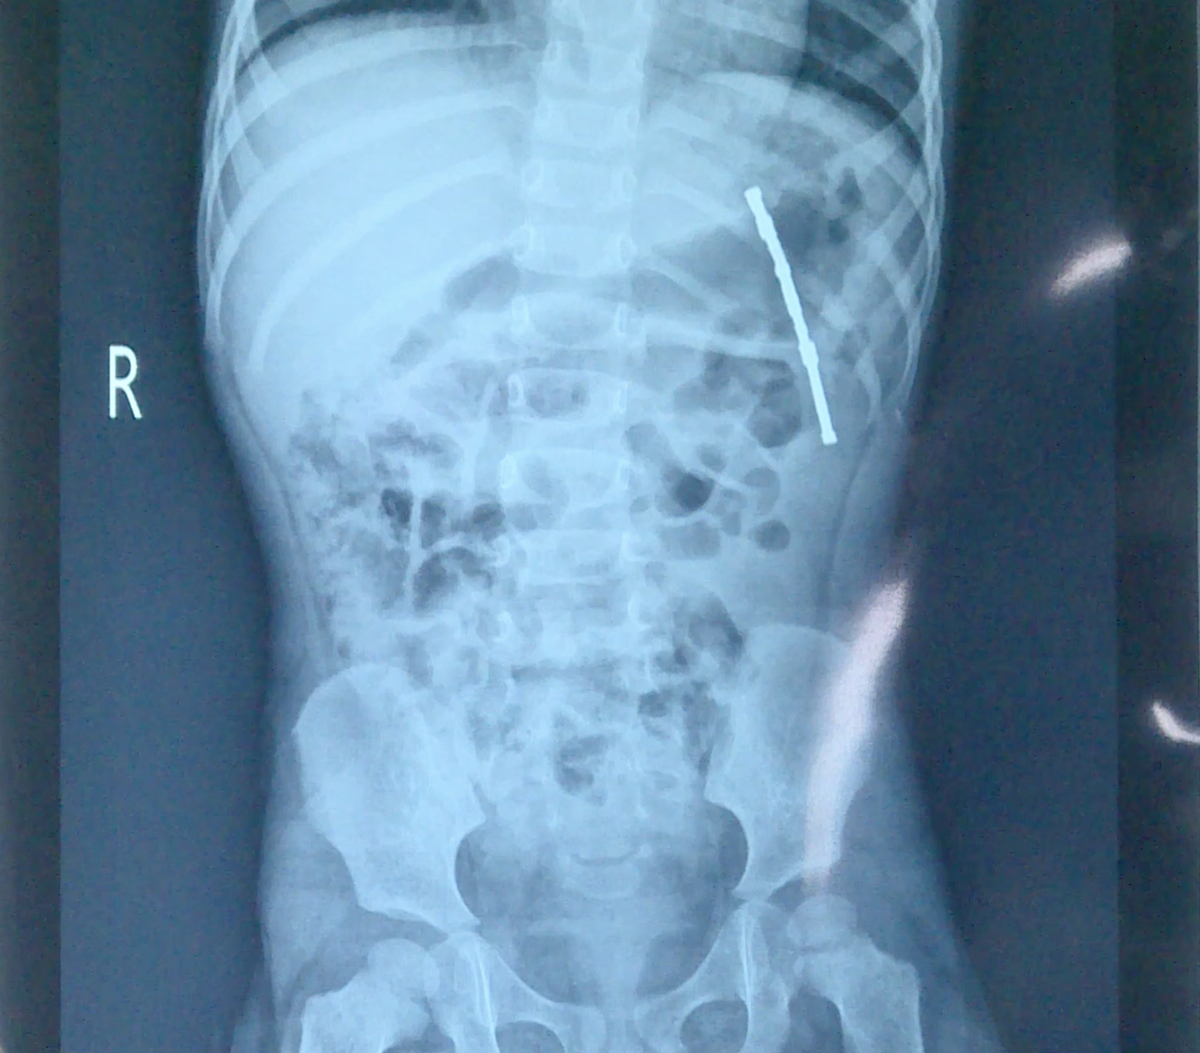

After conducting an ultrasound and X-ray, doctors found a highly visible foreign object in the child’s intestines and decided to admit her to the hospital. Later that afternoon, the doctors performed an emergency gastroscopy for the child.

| An X-ray image shows foreign objects in the girl’s intestines. Photo: A.B. |

The doctors discovered 11 magnets in the child’s stomach arranged vertically, pressing against the lower part of the stomach.